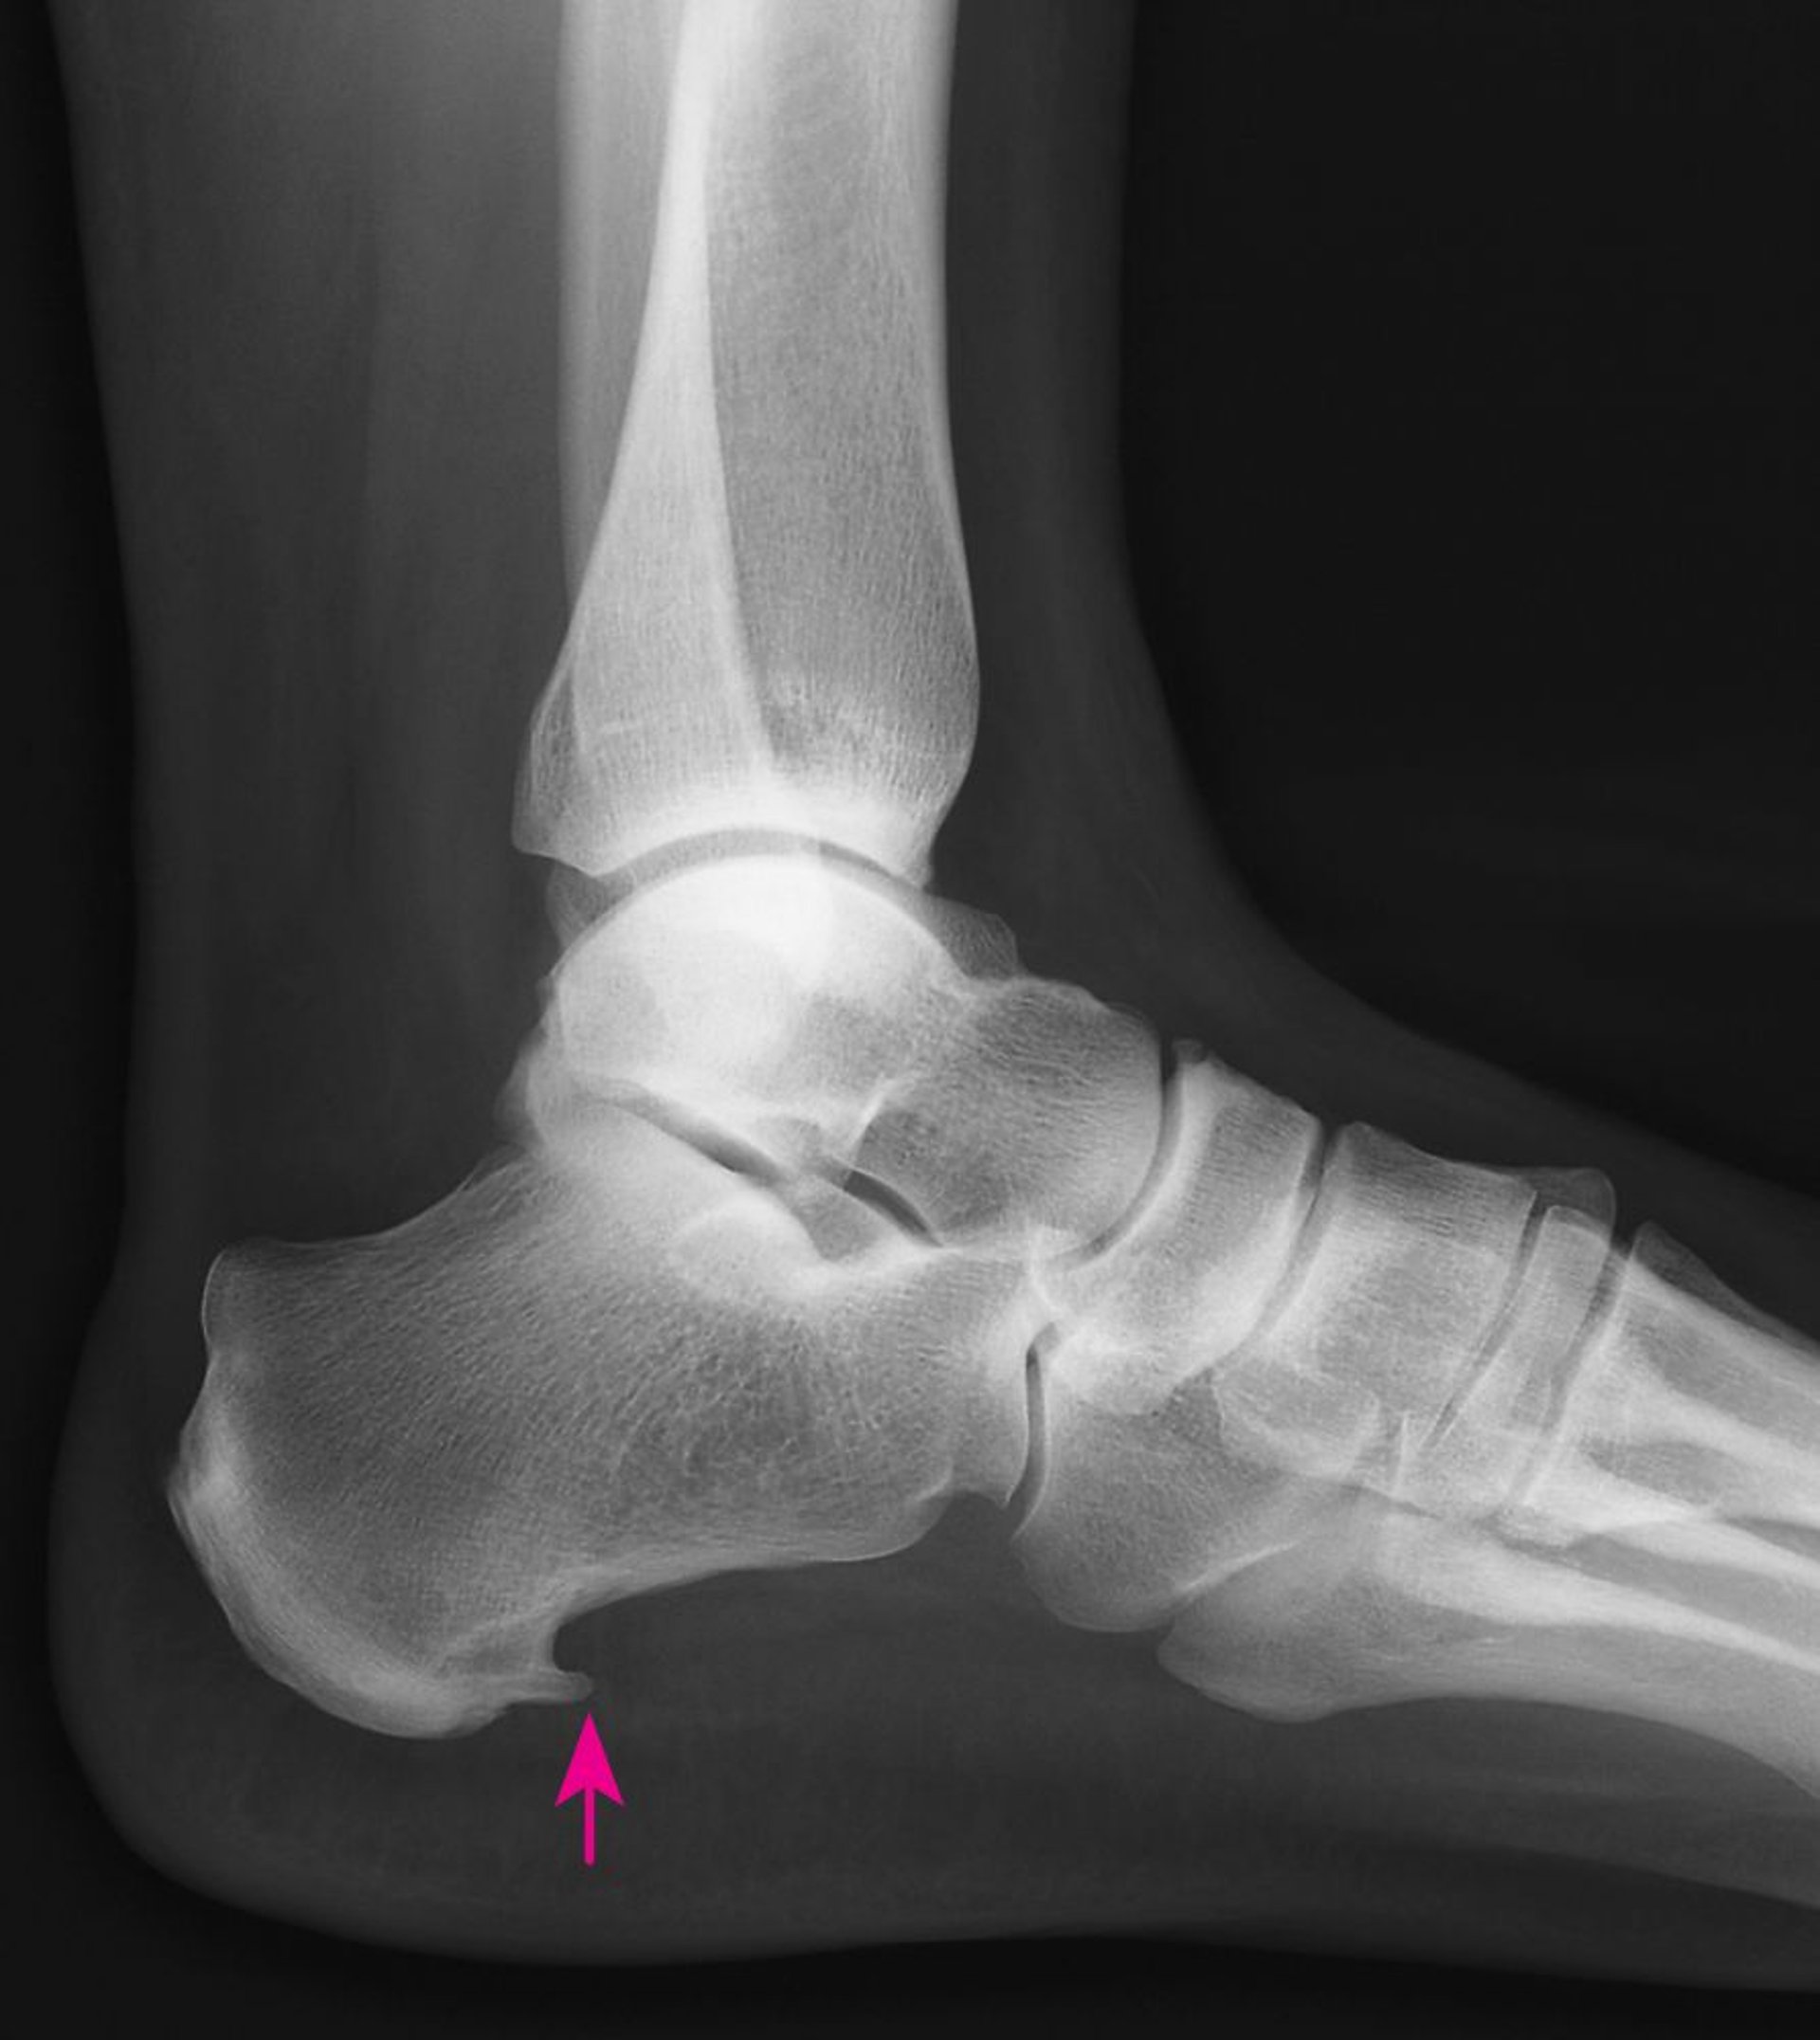

Questa radiografia mostra una spina calcaneare, una neoformazione ossea di forma appuntita sulla parte inferiore del calcagno (freccia).